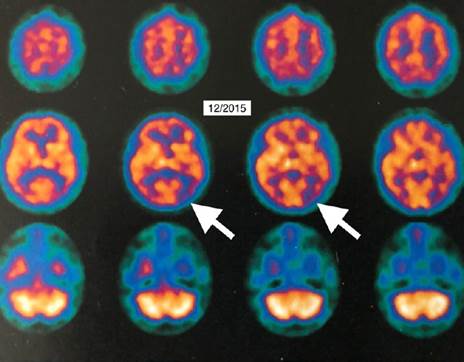

Linda, age 58, was diagnosed with age-related memory loss. For eight months, it rapidly progressed. But after using this "1-hour technology," her brain dramatically changed.

Look at the brain scans...

This “1-Hour Technology” enhances your brain’s ability to repair itself…greatly improving cognitive health.

It's like her brain came back "online!" and she felt it, too. She felt massive improvements in energy and mood. She could solve crossword puzzles, draw a correct clock face and go about her daily living without help.

Most importantly — her brain function improved.

But now, using this "1-Hour Technology," Linda's brain had restored its God-given ability to repair itself.